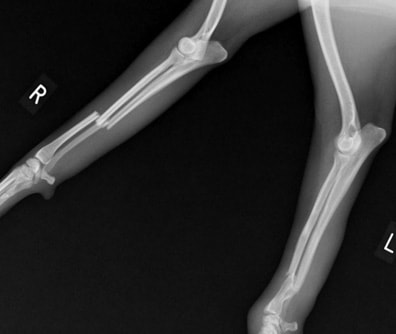

両前肢の骨折:橈骨尺骨骨折整復手術②

![]() 手術前レントゲン写真① |

![]() 手術後レントゲン写真① |

![]() 手術前レントゲン写真② |

![]() 手術後レントゲン写真② |